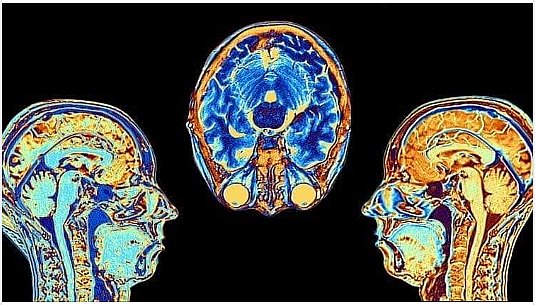

Narušením činnosti mozku je možné ovlivnit mravní hodnocení lidí.

V roce 2010 neurovědci z MIT ukázali , že mohou ovlivnit úsudek lidí tím, že zasahují do aktivity v určité oblasti mozku. Tento objev podle nich pomáhá pochopit, jak mozek „konstruuje morálku“. Oblast mozku známá jako pravý temporoparietální ganglion je velmi aktivní, když přemýšlíme o záměrech, myšlenkách a přesvědčeních jiných lidí. Vědci narušili aktivitu v této části mozku indukcí proudu magnetickým polem aplikovaným na pokožku hlavy. Zjistili, že schopnost subjektů činit morální úsudky, které vyžadují pochopení záměrů jiných lidí – jako je neúspěšný pokus o atentát – byla narušena. Vědci použili neinvazivní techniku známou jako transkraniální magnetická stimulace k selektivnímu zásahu do mozkové aktivity. Magnetické pole působící na malou oblast lebky vytváří slabé elektrické proudy, které narušují normální fungování blízkých mozkových buněk.

Lian Yang, výzkumník z oddělení mozkových a kognitivních věd, věří, že tato část mozku je kritická pro vytváření morálních úsudků: „Považujete morálku za chování na vysoké úrovni. Za normálních okolností jsou lidé v tomto druhu morálního úsudku velmi sebevědomí a důslední. Být schopen ovlivnit (magnetickým polem) určitou oblast mozku a změnit morální úsudek lidí je úžasné. Úplně to nemění morální soudy lidí, pouze je deformuje.“

Jsme obklopeni elektromagnetickými poli a tento nápor každým rokem roste. Od veřejného oznámení této neinvazivní technologie uplynulo 13 let, kam až mohli zajít v její praktické aplikaci?